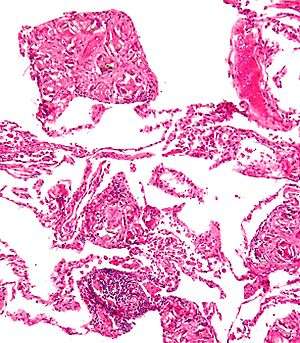

Foreign bodies in the peritoneum eventually become contained in a foreign body granuloma. In the extremely rare case of retained ectopic pregnancy, this forms a lithopedion